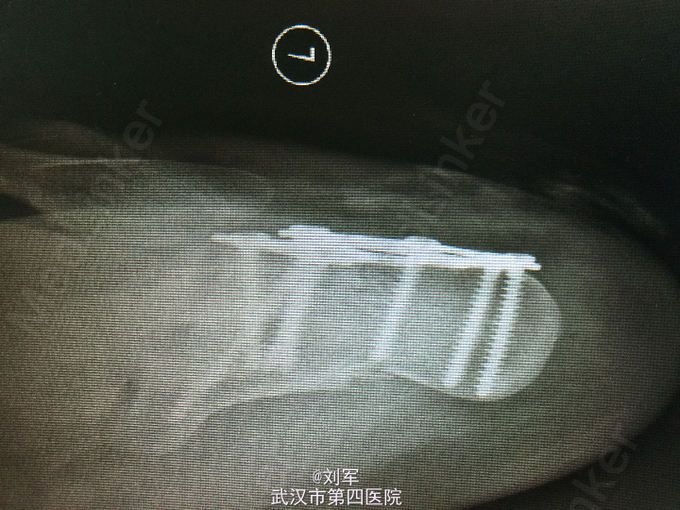

左足跟肿胀,瘀斑,局部压痛及叩痛。左踝活动受限。足趾血运可,感觉存在。左跟骨CT平扫+三维重建:跟骨粉碎性骨折。

左跟骨粉碎性骨折。 入院后完善检查,入院后第六天行开放复位内固定术。

跟骨骨折为创伤骨折常见病,多因高处坠下,足跟着地致伤。根据跟骨CT平扫+三维重建检查,决定治疗方案。